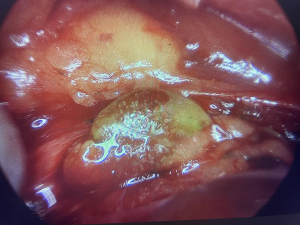

Some studies evaluating the effectiveness of NIR have primarily used the technology to examine the extracted thyroid specimen for inadvertently removed parathyroids, thereby allowing the opportunity to reimplant (12,13). In our institution, we utilize the technology throughout the operation to assist in confirmation of parathyroid tissue in situ. We have found value in instances where parathyroid tissue may be difficult to differentiate from nodal tissue, fat, atypical thyroid nodular tissue or found in an intracapsular position. Figure 5 demonstrates visual contrast between fat and parathyroid tissue, allowing intra-operative differentiation. This may especially be useful in cancer cases where resection margins are paramount, as is removal of any suspicious extra-thyroidal tissue. The NIR camera is yet to be trialled as an adjunct in central neck dissection, but we anticipate it to be useful in improving efficiency and reducing inadvertent parathyroidectomy while maintaining oncologic outcome. If there is tissue suspected to be normal parathyroid in the central nodal compartment, use of the NIR camera would allow for quick identification and confirmation. This may minimize reliance on frozen section analysis and avoid the risk of retained disease or unnecessary parathyroid gland sacrifice when in close proximity to pathologic lymph nodes. In this study, of the 13 patients who underwent central neck dissection (all by naked eye detection only), there were seven cases of inadvertent parathyroidectomy. We believe that NIR may play an important role in balancing parathyroid preservation with thorough resection of malignancy.

One of the main limitations of NIR detection is the depth of penetration. Adipose tissue or thick fascia covering the gland can impede fluorescence signalling. This thus requires proper exposure of the tissue to allow for NIR analysis, risking excess dissection and devascularisation. Furthermore, the endoscope must be relatively close to the gland to induce fluorescence (some sources state 2–3 mm). Because of these aspects, the device is more adept at confirming a surgeon’s suspicions for parathyroid tissue, as opposed to being used to localize the gland. The level of fluorescence can also be variable and difficult to pick up, requiring operating room lights to be switched off temporarily. Parathyroid fluorophores persist after extraction, even up to 2 years (15). As such, even a devascularized parathyroid exhibits fluorescence, and the NIR response is not indicative of intact function. Nevertheless, it can still be used to guide careful dissection around confirmed parathyroid tissue.